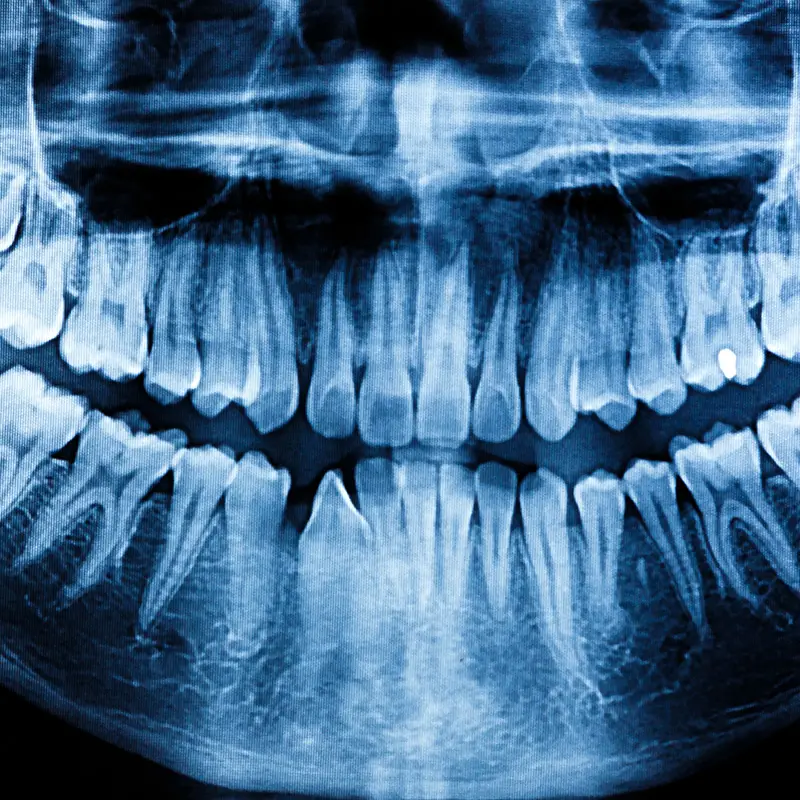

South Shore Dental Arts proudly offers state- of -the -art digital dental radiographs, a cutting edge technology revolutionizing patient care in dentistry. Unlike traditional x-rays, digital radiographs utilize advanced digital sensors to capture highly detailed images of the teeth, bone, and surrounding structures with unparalleled clarity and precision.

Digital dental radiographs are advanced imaging techniques used in dentistry to capture detailed images of the teeth, bone and surrounding structures using a digital sensor in place of traditional x-ray film.

Unlike traditional x-rays, which use film to capture images and require chemical processing, digital dental radiographs utilize digital sensors to produce instant, high-quality images that can be viewed on a computer screen. Digital radiography also reduces radiation exposure and offers enhanced diagnostic capabilities.

Yes, digital dental radiographs provide superior image quality compared to traditional x -rays. The digital sensors used in digital radiography produce highly detailed images that can be magnified, enhanced, and manipulated for better visualization of dental structures, aiding in more accurate diagnoses and treatment planning.